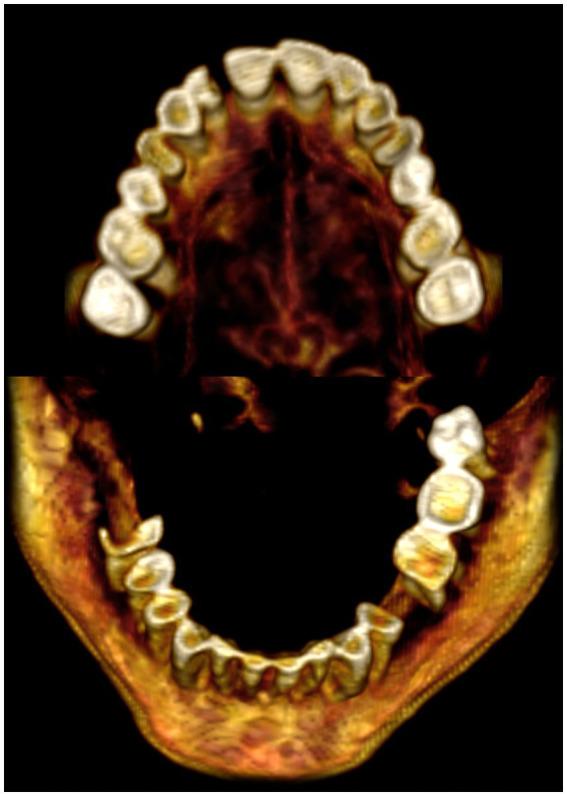

Computed tomography estimated the age of death to be 48.1 years ±14.6 based on the pubic symphyseal surface. CT detected mild-to-moderate teeth attrition, and joints degeneration. The desiccated brain and viscera remained . FTIR revealed the wig is formed of midrib date palm that shows in CT as spiral low density fibers. The wig fibers are partially coated with a thick substance that is inspected as black consolidation and identified as crystalline by XRD, comparable to material found in an ancient wig-making workshop. FTIR showed that the skin, hair, and wig samples were treated with imported juniper resin had anti-bacterial and insecticidal properties. The skin and wig samples contained frankincense, and the hair sample contained henna.

基于耻骨联合面,CT估计死亡年龄为48.1岁±14.6岁。CT检测到轻度至中度的牙齿磨损和关节退变。干燥的大脑和内脏得以保留。FTIR显示假发由枣椰树的中脉形成,在CT中表现为螺旋状低密度纤维。假发纤维部分被一种厚实物质覆盖,在CT中被检测为黑色固结物,经XRD鉴定为晶体,与在一个古代假发制作工坊中发现的材料类似。FTIR表明皮肤、头发和假发样本用具有抗菌和杀虫特性的进口杜松树脂进行了处理。皮肤和假发样本含有乳香,头发样本含有指甲花。